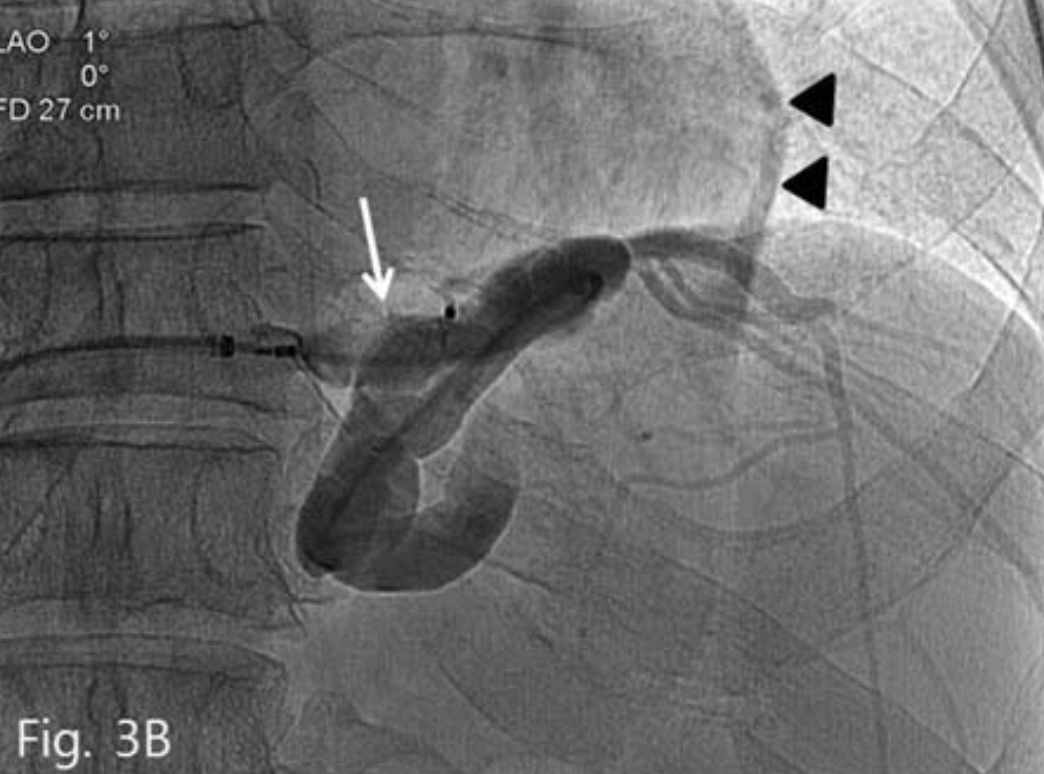

우측 총대퇴정맥을 통해 7-Fr sheath(Flexor Check-Flo; Cook, Bloominglon, IN, USA)를 삽입 후 5-Fr Cobra catheter(Cook)와 0.035-inch guidewire(Terumo, Tokyo, Japan)로 위대정맥단락를 동해 위정맥류 내부로 catheter를 진입시켰다. 시행한 정맥조영술에서 위정맥류 일부와 왼쪽 횡경막하 정맥이 보였으며 조영제는 위대정맥단락과 심장막정맥 (pericardial vein)을 통해 유출되고 있었다(Fig. 3A).

A. Venogram shows gastrocaval shunt, gastric varices, left inferior phrenic vein and pericardial vein.